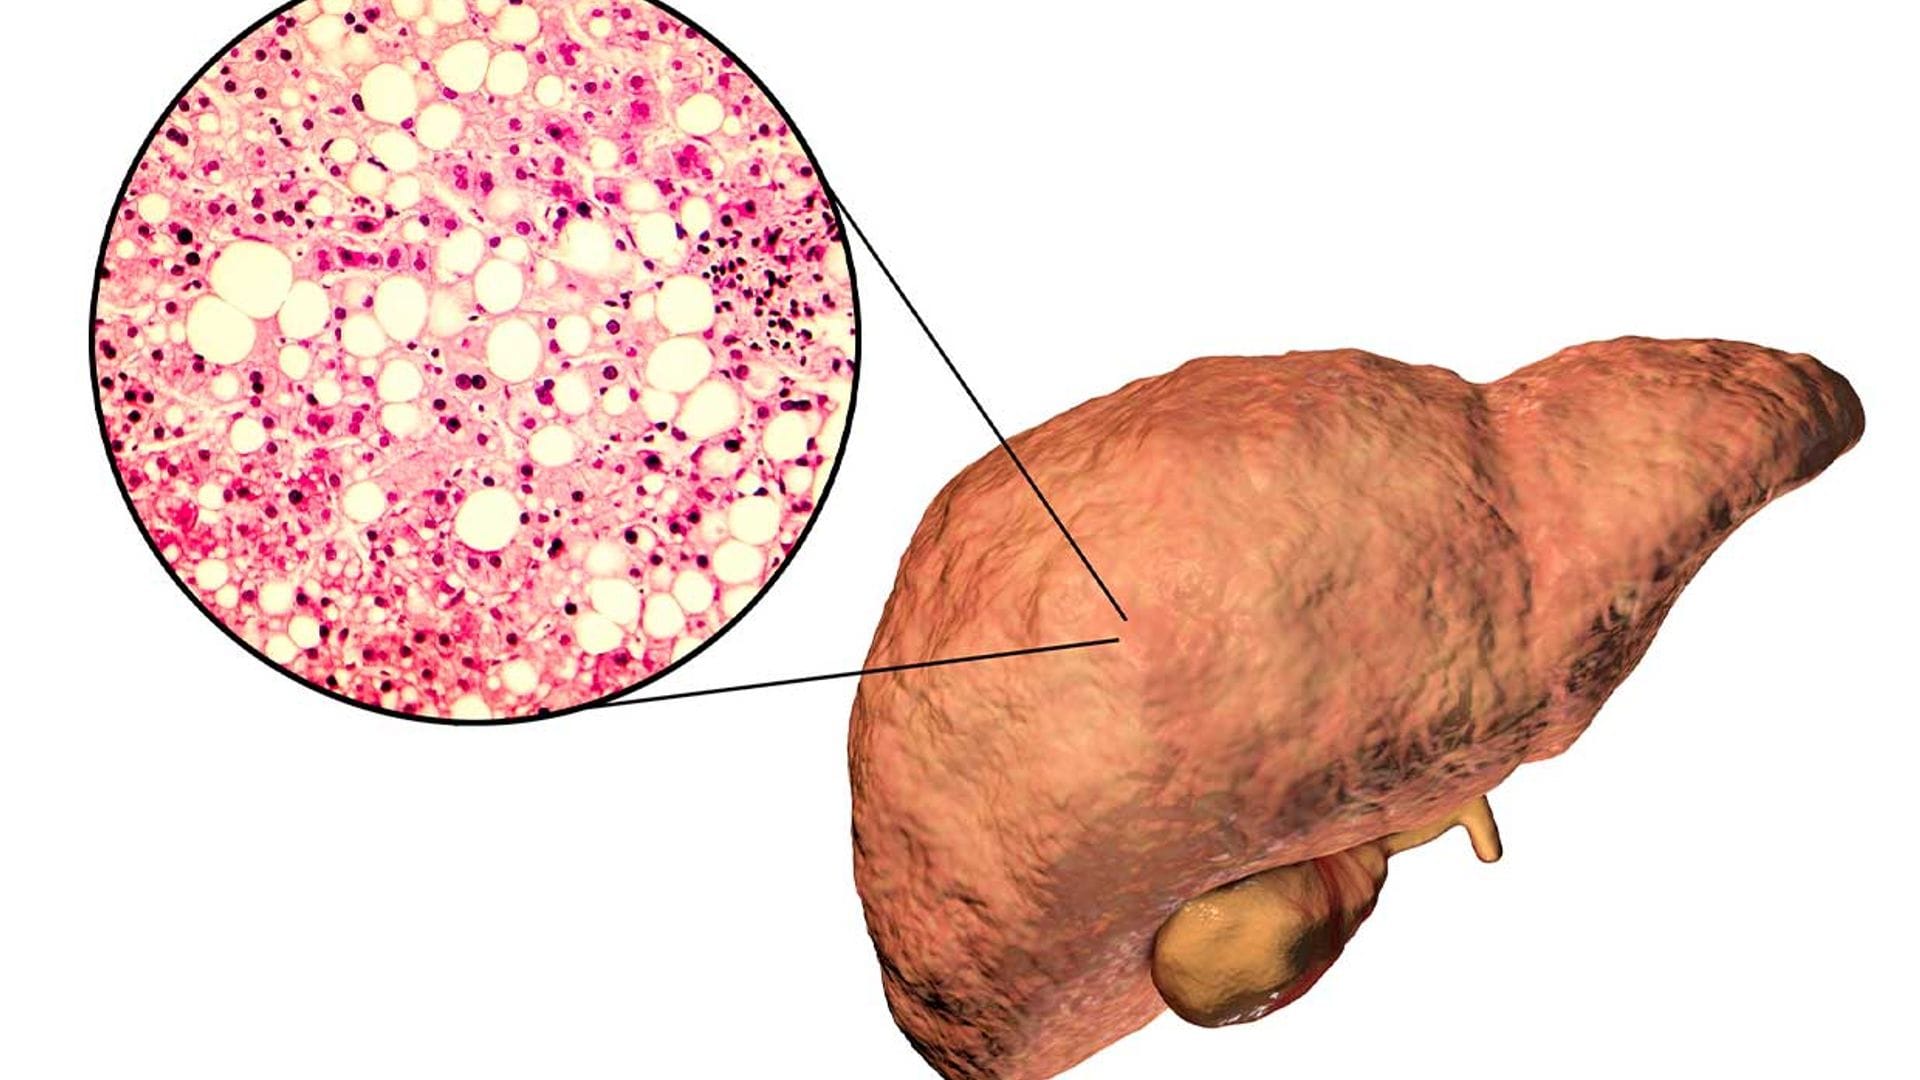

El hígado graso es una de las dolencias más habituales del hígado.

En breves palabras, podemos definir el hígado graso como un cúmulo de grasa alrededor del órgano, principalmente triglicéridos, y cuando este porcentaje de grasa es mayor que el propio volumen del hígado (aprox. 5%), el problema no solo es la acumulación de grasa sino también la inflamación e irritación del propio hígado, lo que provoca un mal funcionamiento.

El hígado graso es una enfermedad o dolencia que puede curarse, es reversible, sobre todo controlando la dieta y el estilo de vida y de hecho debe tratarse para evitar que se convierta en una enfermedad irreversible.

DIFERENTES TIPOS DE HÍGADO GRASO

Hígado graso no alcohólico

Suele ocurrir cuando el hígado tiene dificultad de digerir las grasas, por lo que se acumulan alrededor del hígado, provocando el mal funcionamiento.

Hígado graso de origen alcohólico

Cuando se bebe demasiado alcohol llega un punto que el hígado se satura y no tienen capacidad de metabolizarlo, por lo que se acumula en el hígado. Puede evolucionar si no se remedia en cirrosis hepática.